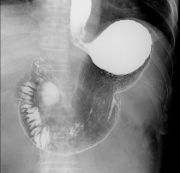

上部消化管検査

下部消化管検査